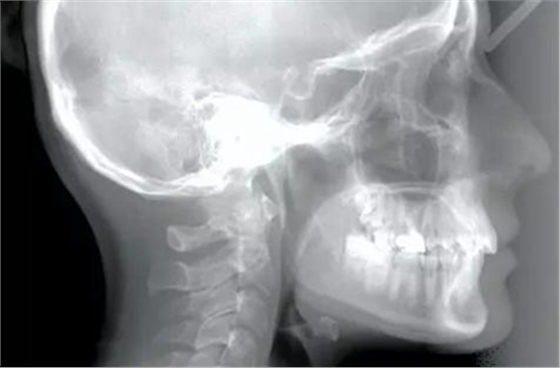

患者為19歲高加索女性,要求矯治中線不齊及上頜右側(cè)側(cè)切牙腭側(cè)異位??趦?nèi)檢查,左側(cè)安氏Ⅰ類尖牙、磨牙關(guān)系,右側(cè)安氏Ⅱ類尖牙、磨牙關(guān)系;上頜中線右偏4mm,下頜中線右偏2mm,16牙根管治療史,16及47有修復(fù)體;覆蓋5mm,覆合4mm,無橫向不調(diào)。功能檢查,顳下頜關(guān)節(jié)無明顯異常,面部及咀嚼肌不對稱。

頭影測量分析顯示,SNA為80.9°,SNB為79.5°,ANB為1.4°,SN-GoMe角為25.5°,下切牙到NA的角度為22°、距離為4mm,上頜切牙與NA角度為18°、距離為4mm,上唇在E線后5mm,下唇在E線后3mm,鼻唇角為110°。